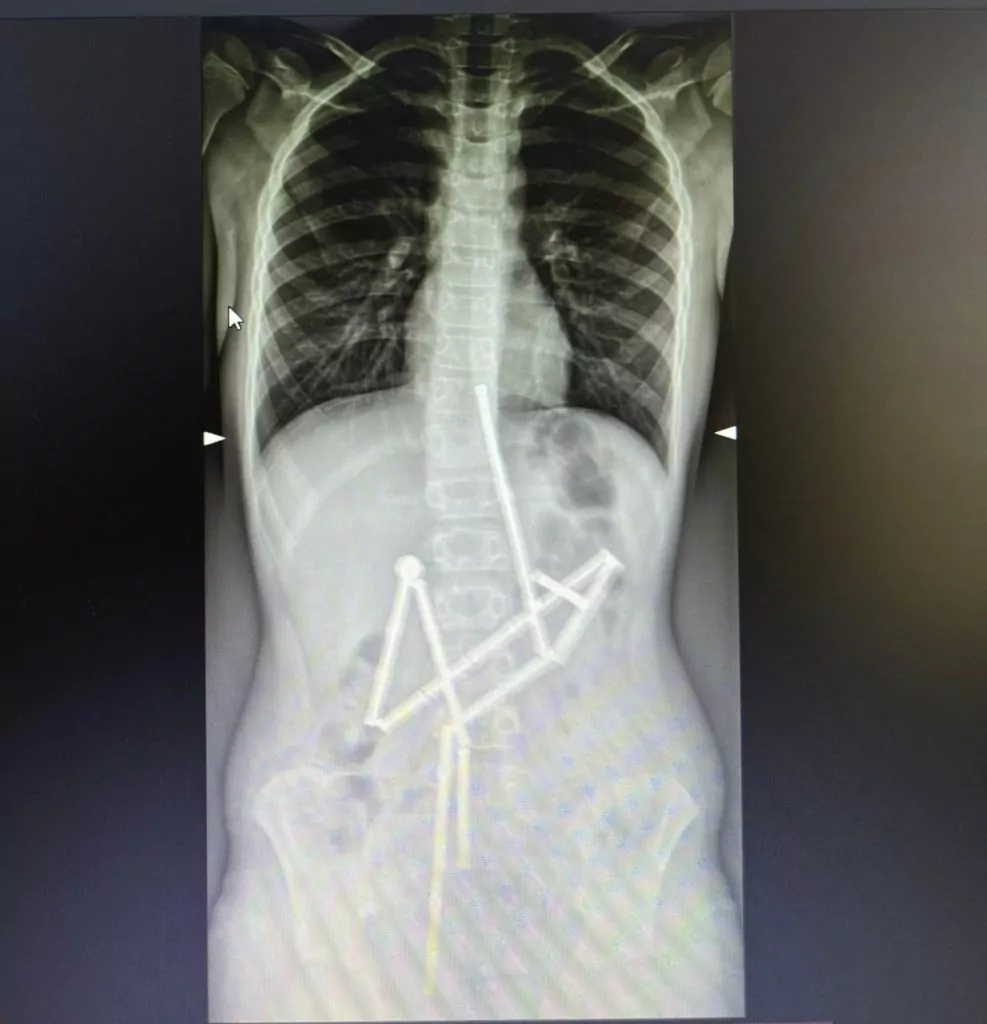

Коли він поскаржився на біль у животі, батьки звернулися до лікарів. Вже перший рентген виявив у травному каналі цілу групу сторонніх тіл, кажуть медики.

Магніти опинилися у різних частинах шлункового тракту, але були з’єднані між собою. Медики вирішили терміново проводити операцію, адже стан хлопчика міг погіршуватися з кожною годиною.

Команда ендоскопістів виявила зчеплені між собою магніти. Вони захопили перший магніт й змогли витягти його разом з ланцюжком з 18-ти інших.

Але один магніт лікарі не змогли видалити ендоскопічно, тож до операції долучились хірурги. Під час огляду органів черевної порожнини у дитини виявили п’ять отворів та останній магніт. Медики витягли його й закрили отвори.